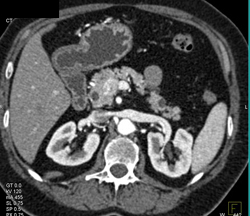

Carcinoma Encases the SMA